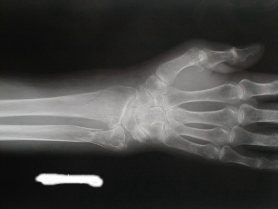

右前腕骨骨折

53日目

日常動作に支障なく経過良好にて治癒とする